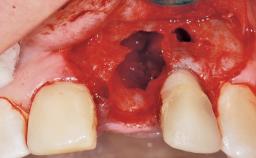

A 42-year-old female patient was referred to our clinic at the School of Dentistry of the University of São Paulo in November 2004, presenting a deficient restoration in the upper left central incisor. The clinical examination revealed no gingival retraction or any signs of gingival inflammation and, therefore, previous periodontal treatment was not considered. The patient presented a high lip line at full smile and a thin tissue biotype. This combination characterized a high-risk situation from an anatomic point of view, which required careful preoperative planning and cautious surgical execution.

Placement Protocol Immediate implant placement

Tooth Site Maxillary incisor or canine

Socket Integrity Sufficient, with intact bone walls

Bone Volume Sufficient, with intact walls